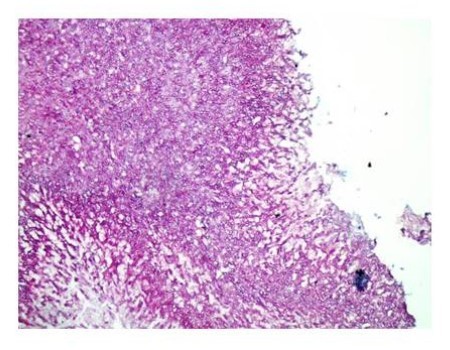

A 64-year-old lady presented to the outpatient department with complaints of headache and right eye blurring of vision for one month. Neurological examination revealed that bitemporal hemianopsia and impairment of visual acuity. Findings from fundus examination were within normal limits. Rest of the brain appeared unremarkable. Endocrine evaluation was normal. Results of renal function tests, liver function tests and haemogram test were within normal limits. A clinical diagnosis of non-secretory pituitary adenoma was made. Magnetic resonance imaging showed a well-circumscribed contrast-enhancing lesion in the sella (Figure 1, Figure 2). The patient underwent an endoscopic endonasal/transsfenoidal surgery in the supine position and total lesion resection was peformed. Intraoperatively, the lesion was found to be yellow colour, soft and avascular and it was removed totally until the sella turcica was visualized (Figure 3).In histopathologic examination septate hyphae were observed between inflammatory cells, Grocott staining is positive, but acid-fast stain for acid-fast bacilli (AFB) was negative. Histopathological findings suggest that infection of Actinomyces (Figure 4, Figure 5). We performed to patient consulted by patients to infectious diseases clinic. Patients underwent intravenous 6x2 gr ampicillin for four weeks.Then oral 4X500 mg amoxicillin treatment is planned a for at least 6 months. Patient did not have any deficits in the next six months.

Figure 4.Light Green PAS stain with filamentous branching bacteria at 10x magnification